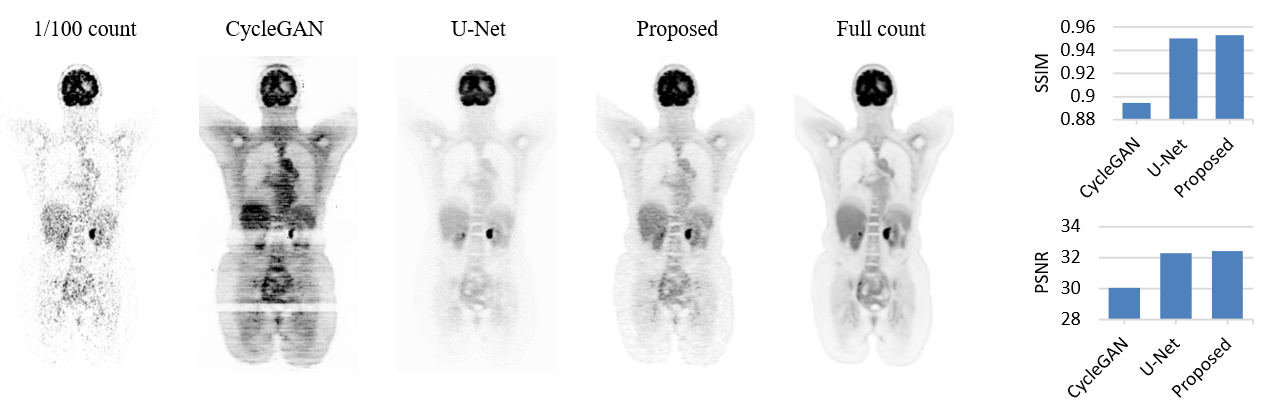

We conducted experiments using the publicly available Siemens Biograph Vision Quadra dataset provided by the Ultra-low Count PET Imaging Challenge [5]. This dataset comprises 387 total-body 18F-FDG PET scans. All data were ac-quired in list mode, enabling retrospective rebinding to simulate various acquisition durations. Simulated low-count PET images, representing reduced dose scenarios with specific dose reduction factor, were reconstructed by resampling counts from a shortened time window centered within the original acquisition period. The resulting images include reconstructions at 1/100, 1/20, 1/10, 1/4, and 1/2 of the full count, as well as the full count image. These varying count levels provide a robust foundation for training and evaluating count-aware denoising models. We used various count level images in the test images to specifically synthesize the full count image with output text of full count level. The visual example of synthetic denoising full count image from various count levels shown in Figure 2. The proposed model can successfully denoise various count levels images to full count PET images. For quantitative evaluation, we denoised images at all count levels to generate synthetic full-count images, then compared the SSIM and PSNR between the original low-count images and the corresponding synthetic full-count images, using the real full-dose image as the reference. The quantitative results which are shown in Figure 3 indicate that denoised images from different count levels are closer to the full count image than the original low count image. We also compared model ability for synthetic full count image from 1/100 count image with U-Net and CycleGAN model, for just testing the ability of the flexible framework, only the baseline methods were compared. Note that the U-Net and CycleGAN model only trained with 1/100 count model and regard full count image as ground truth. As shown in Figure 4, regarding the visual results, the proposed method is closer to the full count, and the PSNR and SSIM of the proposed method is higher than the U-Net and CycleGAN models.

To assess the effectiveness of the proposed model, and given the absence of an existing baseline with similar functionality, we compared it with U-Net and CycleGAN under the same task of denoising 1/100-count images to full-dose equivalents. Experimental results demonstrate that our model achieves superior performance in terms of SSIM and PSNR across multiple count levels, validating its adaptability and robustness. This work introduces new possibilities for count-controllable PET reconstruction, which is particularly valuable in clinical and research settings where balancing radiation exposure and image quality is critical. However, the current study is limited by the availability of paired input–output data. In future work, with access to sufficient raw list-mode PET data, arbitrary dose-level PET images could be simulated, further enhancing the flexibility and applicability of the proposed approach.